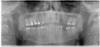

Bier Опубликовано 5 июля, 2010 Поделиться Опубликовано 5 июля, 2010 снимки зубов нужны, возможно можно просто пролечить зубы у стоматолога и долечить пазуху. Ссылка на комментарий

Slavik111 Опубликовано 5 июля, 2010 Автор Поделиться Опубликовано 5 июля, 2010 (изменено) Спасибо за ответ.Вот панорама.Вывод о том, что после удаления 16 и 17 образуется соустье, хирург сделал после просмотра 3Д снимка - это большая программа, ее сюда не закачать. Изменено 5 июля, 2010 пользователем Slavik111 Ссылка на комментарий

Slavik111 Опубликовано 6 июля, 2010 Автор Поделиться Опубликовано 6 июля, 2010 Согласен. + Все может оказаться еще проще, удалят, сообщения не будет, гайморит пройдет быстро. Насчет сообщения - я специально 4 снимка 17-го зуба приложил - там с моей точки зрения корни прямо в пазуху торчат (если это однородное пространство над корнем - пазуха).Или я не прав и это не пазуха? Большое спасибо за советы! Только что был на приеме у ЛОРа. 9-я пункция - вытянула немного (может 5 мл) шприцом желтого полупрозрачного секрета - сказала что киста. Затем промывала долго - 2 банки вылила - гной только вначале, примерно 1 чайная ложка (может меньше). По сравнению с позапрошлым разом - гораздо меньше.Извините, уважаемые, но несмотря на Ваши советы подписал отказ от госпитализации.След. пункция в четверг. ЛОР сердилась за мой отказ,сказала что меньше гноя уже не будет, но затем смягчилась (потому что ничего больше у меня не болит и насморка нет) и сказала что решим по результатам пункции в четверг.На самом деле я буду думать - я понимаю что в стационаре лучше, но раз все-таки меня соблазнили "более легким" путем - если без гноя то амбулаторно - то получается есть из чего выбирать. В черьверг, чувствую, уже не будет из чего выбирать Ссылка на комментарий